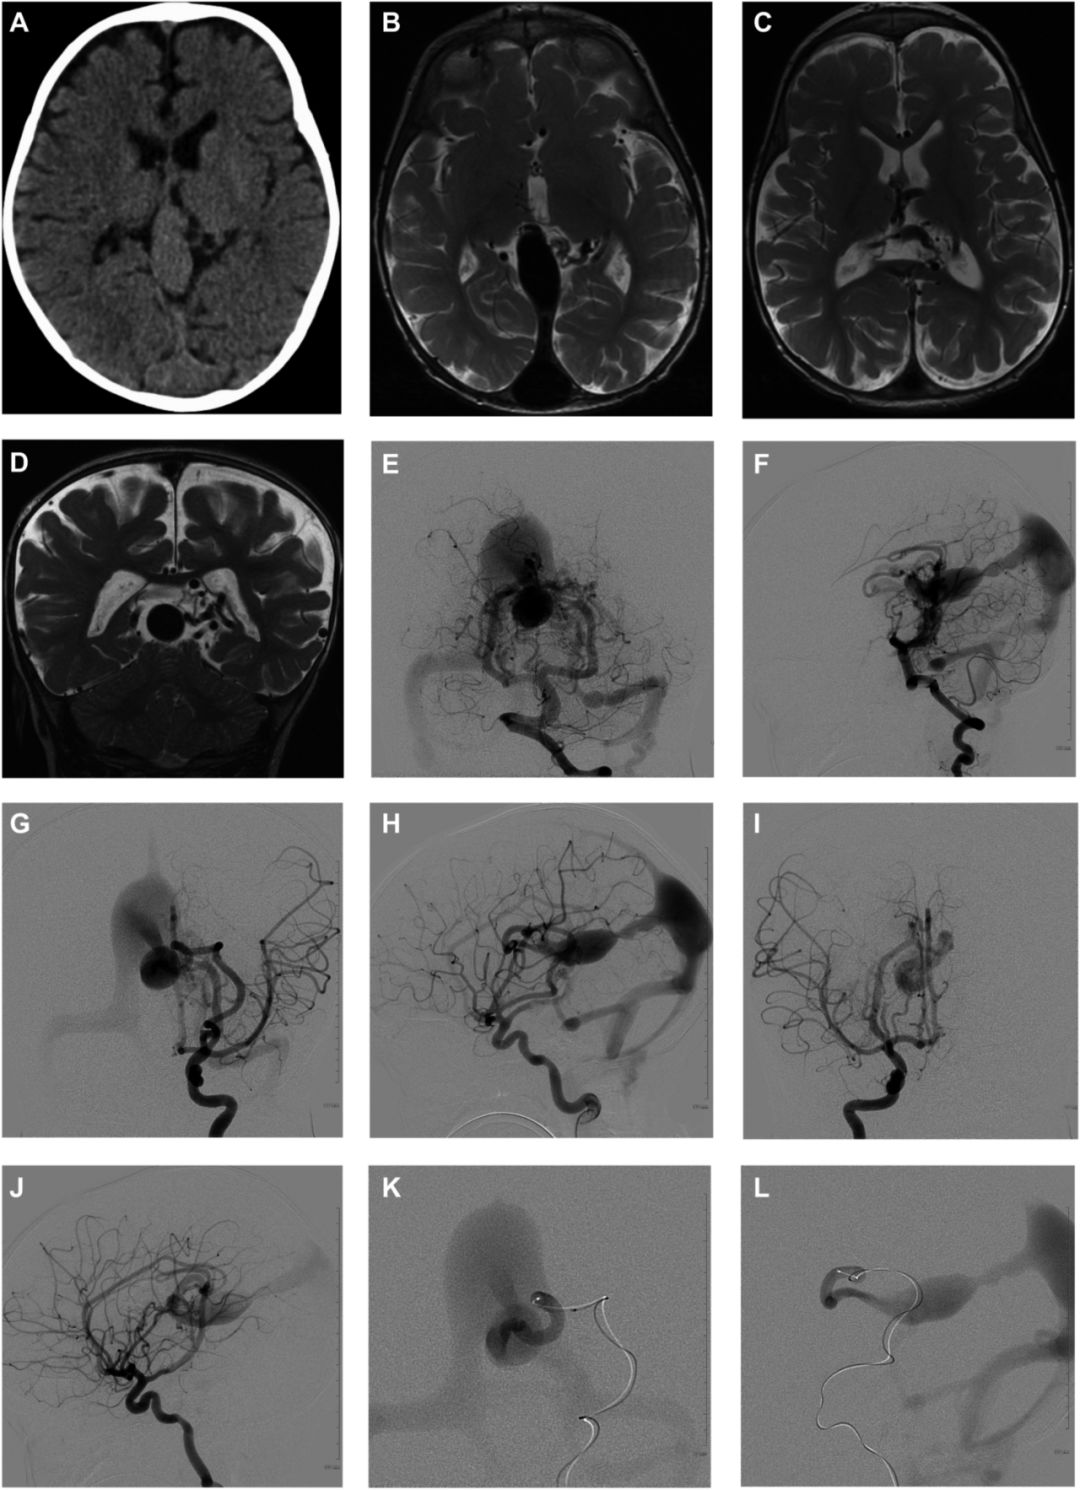

图3 A-B 大脑前动脉超选示另一供血动脉,C 首次栓塞后注胶,D 残余瘘口,E-F 6个月后二期手术,可见残余瘘口,G-H 二期手术后血供显著减少,I-N 6个月后造影示VGAM完全栓塞,O-P MR示完全栓塞,脑组织发育正常、MRA示正常血管网。